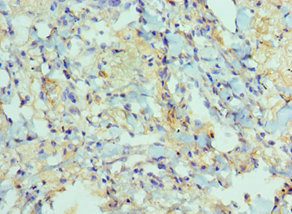

圖片:

應用范圍:ELISA, IHC

Application Recommended Dilution IHC 1:20-1:200 -